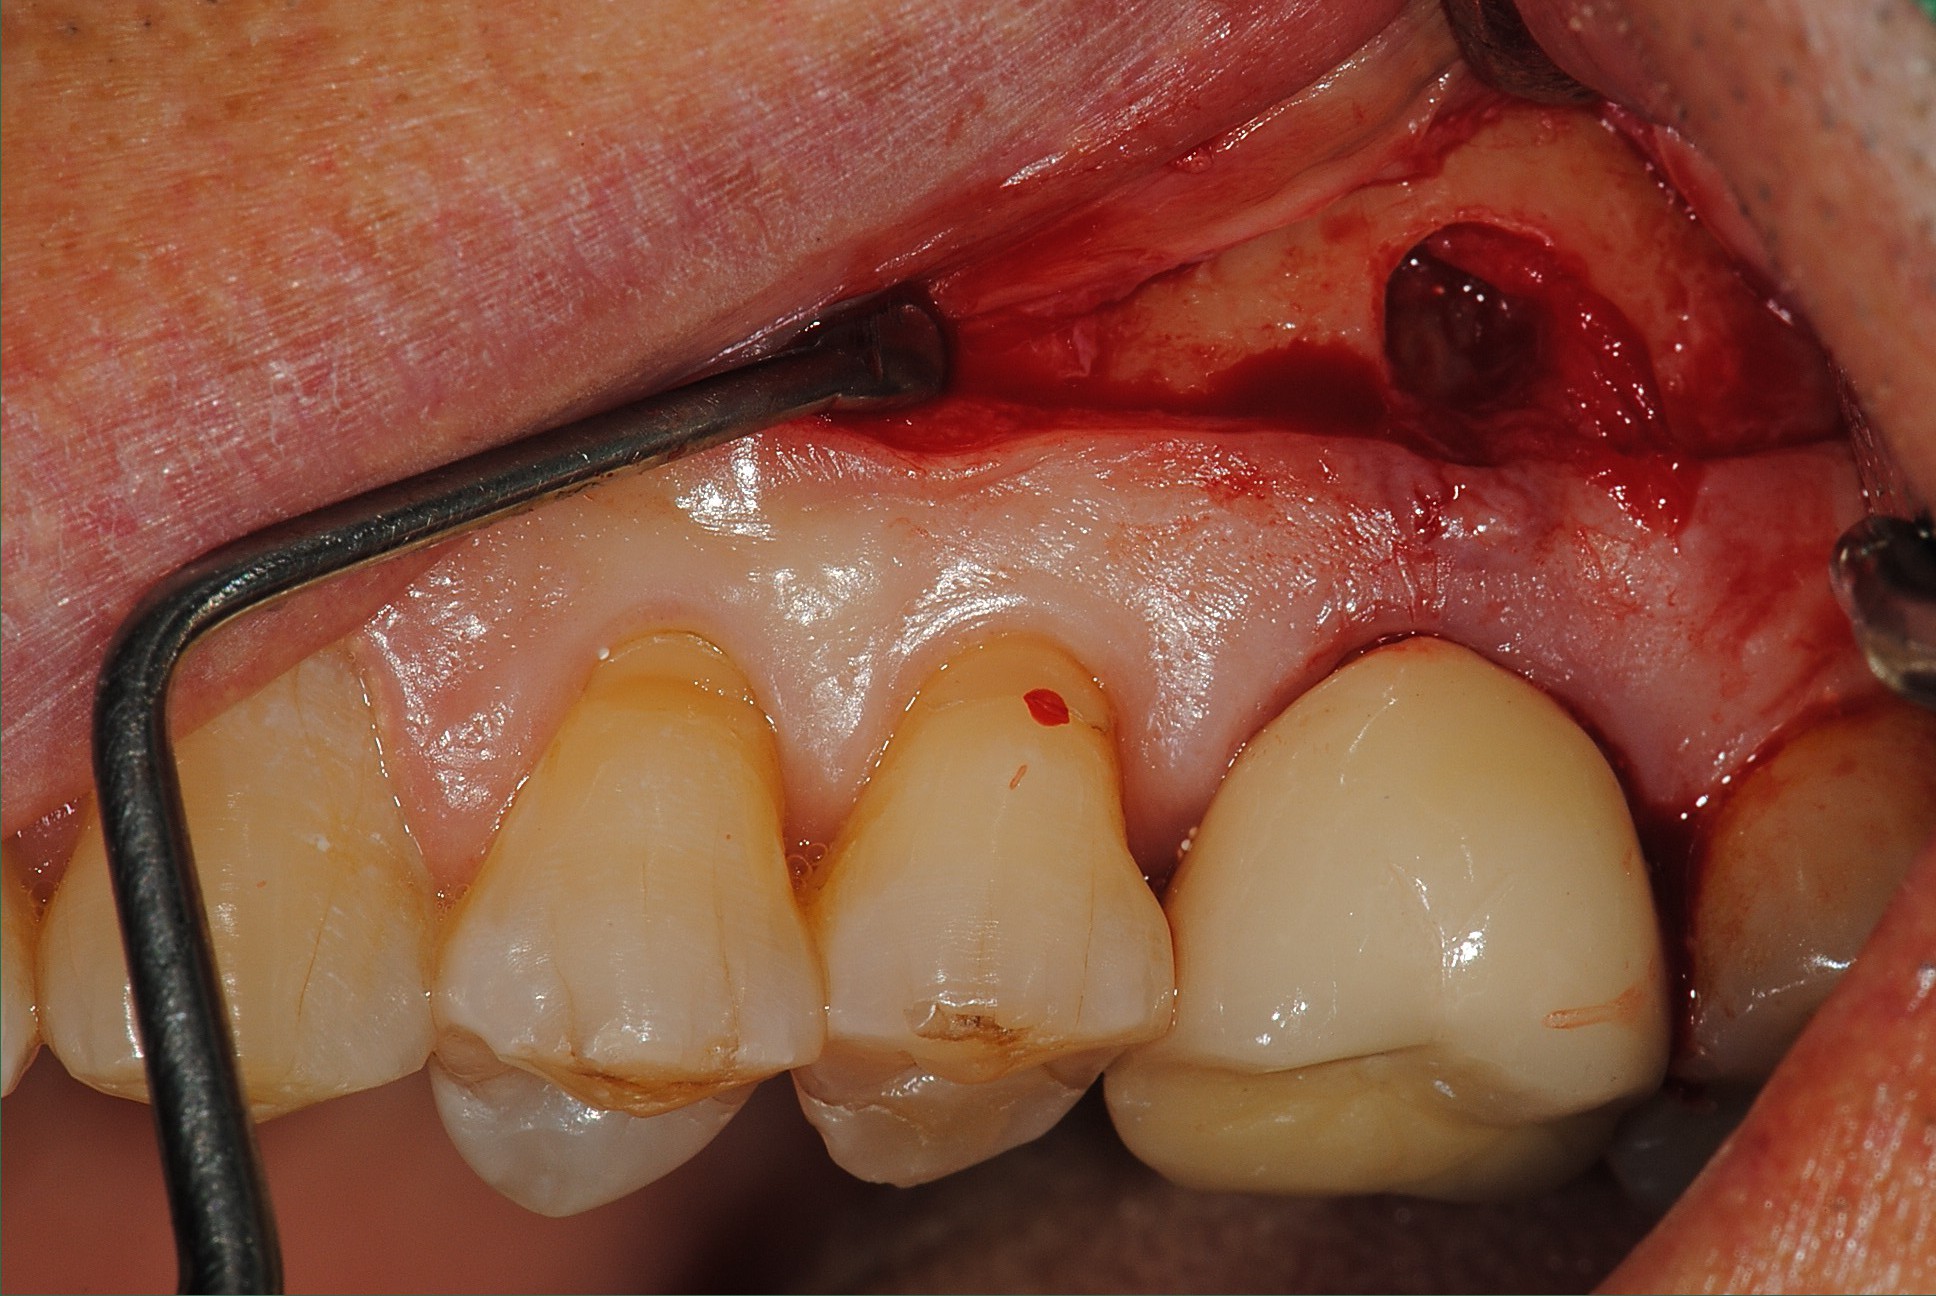

치관확장술의 적용사진입니다.